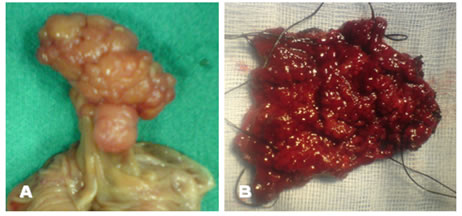

Μακροσκοπικά, διακρίνονται σε έμμισχους και άμισχους (Εικόνα 1).

Εικόνα 1.

Α. Έμμισχος σωληνολαχνωτός αδενωματώδης πολύποδας που αφαιρέθηκε χειρουργικά.

Β. Ευμεγέθης άμισχος λαχνωτός αδενωματώδης πολύποδας ορθού που αφαιρέθηκε χειρουργικά διά του ορθού.

(Από το προσωπικό αρχείο του Γ. Θεοδωρόπουλου)